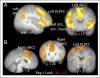

Craving of unhealthy food is a common target of self-regulation, but the neural systems underlying this process are understudied. In this study, participants used cognitive reappraisal to regulate their desire to consume idiosyncratically craved or not craved energy-dense foods, and neural activity during regulation was compared with each other and with the activity during passive viewing of energy-dense foods. Regulation of both food types elicited activation in classic top-down self-regulation regions including the dorsolateral prefrontal, inferior frontal, and dorsal anterior cingulate cortices. This main effect of regulation was qualified by an interaction, such that activation in these regions was significantly greater during reappraisal of craved (versus not craved) foods and several regions, including the dorsolateral prefrontal, inferior frontal, medial frontal, and dorsal anterior cingulate cortices, were uniquely active during regulation of personally craved foods. Body mass index significantly negatively correlated with regulation-related activation in the right dorsolateral PFC, thalamus, and bilateral dorsal ACC and with activity in nucleus accumbens during passive viewing of craved (vs. neutral, low-energy density) foods. These results suggest that several of the brain regions involved in the self-regulation of food craving are similar to other kinds of affective self-regulation and that others are sensitive to the self-relevance of the regulation target.